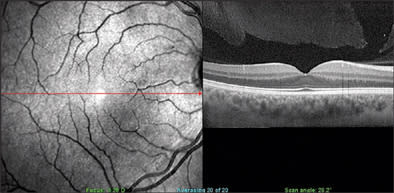

Figure 2. Normal retinal exam with overlying vitreous gel liquefaction and partial separation of posterior hyaloid face nasal to the fovea.

PHOTO COURTESY OF RICHARD B. ROSEN, MD

The Spectral OCT SLO Combination Imaging System (OPKO Health, Inc., Miami) performs a variety of scans while simultaneously producing a scanning laser ophthalmoscope (SLO) image for real-time registration. "It gives you perfect correspondence between the surface and cross-sectional anatomy, so you know exactly where the scan for the cross-section is taken," says Richard B. Rosen, MD, vice chairman and director of research, New York Eye and Ear Infirmary.

Clinicians can use blood vessels on the fundus image to align images, enabling them to obtain precise thickness maps incorporating a large number of cross-sections, Dr. Rosen says. Thickness maps can be rendered into 3-dimensional images, so that clinicians can scan through the retinal thickness map and view the OCT images beneath.

Thickness maps have a variety of configurations, Dr. Rosen says, corresponding to the ETDRS, showing critical target areas for treatment. "You can also overlay onto these thickness maps a whole system of microperimetry," he says. Using microperimetry, which is available as an add-on feature, the clinician can match a point of reduced sensitivity with OCT findings at the same point, for example.